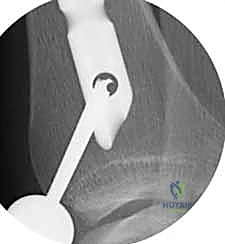

4. إدخال المسمار النخاعي والتثبيت النهائي

يتم تمرير مسمار التيتانيوم بدقة داخل العظم. وبمجرد التأكد من موضعه المثالي بالأشعة، يقوم البروفيسور هطيف بإدخال المسامير التشابكية (Locking Screws) العرضية في أعلى وأسفل المسمار لضمان التثبيت المطلق.

- التثبيت التشابكي (Interlocking): يتم تمرير مسامير صغيرة عرضية عبر العظم والمسمار النخاعي في الطرفين العلوي والسفلي، مما يمنع دوران العظم حول المسمار ويحافظ على طول الساق الطبيعي بدقة متناهية.